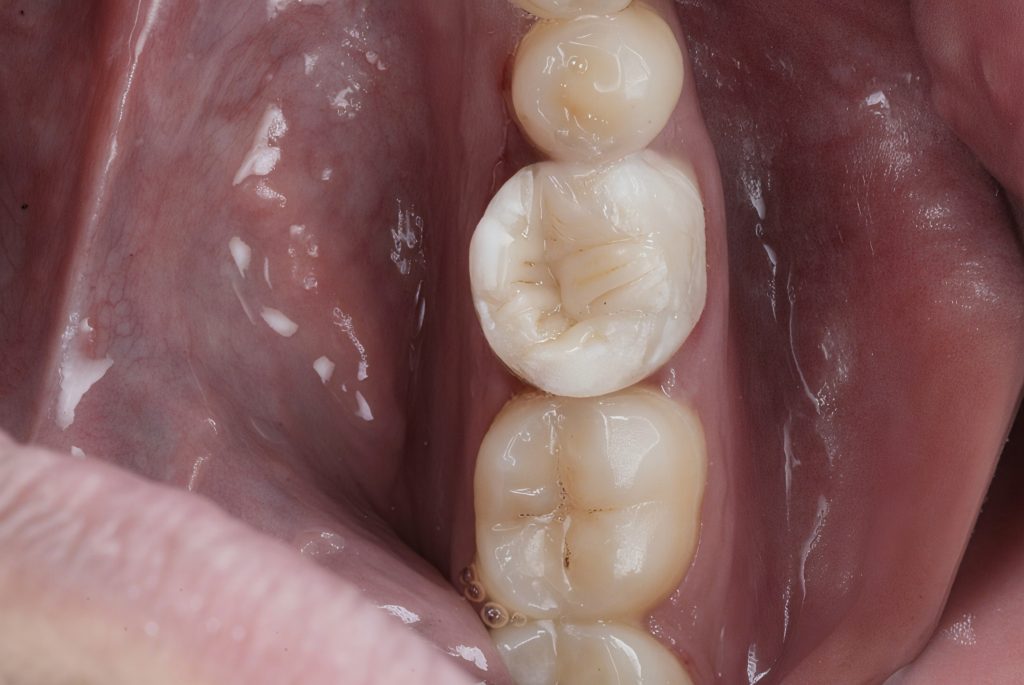

A 24-year-old patient presented with spontaneous pain on biting and tenderness localized to the mandibular right first molar (#46). Clinical examination revealed a large defective composite restoration with underlying recurrent caries. The tooth tested symptomatic irreversible pulpitis with normal periapical findings. Preoperative periapical radiograph showed deep recurrent caries approaching the pulp with no periapical radiolucency.

Cuspal coverage was achieved with a biomimetic direct onlay design to redistribute occlusal forces and prevent fracture.

Anatomy sculpted following natural occlusal morphology. Final finishing and polishing was done using Lucida Star + Spiral Polishers (Style Italiano) for enamel-like luster.

- Tooth was functionally and esthetically restored in a single visit.

- No post-op pain at 7-day recall, excellent function and marginal seal.